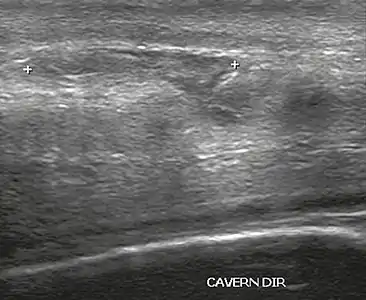

Venous drainage is performed by the deep and superficial dorsal veins of the penis. The dorsal arteries of the penis are located adjacent to the deep dorsal vein and a cavernous artery is located in the center of each corpus cavernosum. On color Doppler, the cavernous arteries present single phase flow. In the flaccid penis (Figure 3), the normal cavernous arteries show a systolic peak between 11 and 20 cm/s. At the beginning of erection, the systolic and diastolic flows undergo progressive increases. When vein occlusion begins, the diastolic flow decreases progressively, and once stiffness is established, it becomes negative.[1]

Figure 3: Longitudinal, ventral ultrasound of the penis, with pulsed mode and color Doppler. Normal flow pattern of the cavernous artery in a flaccid penis.[1]